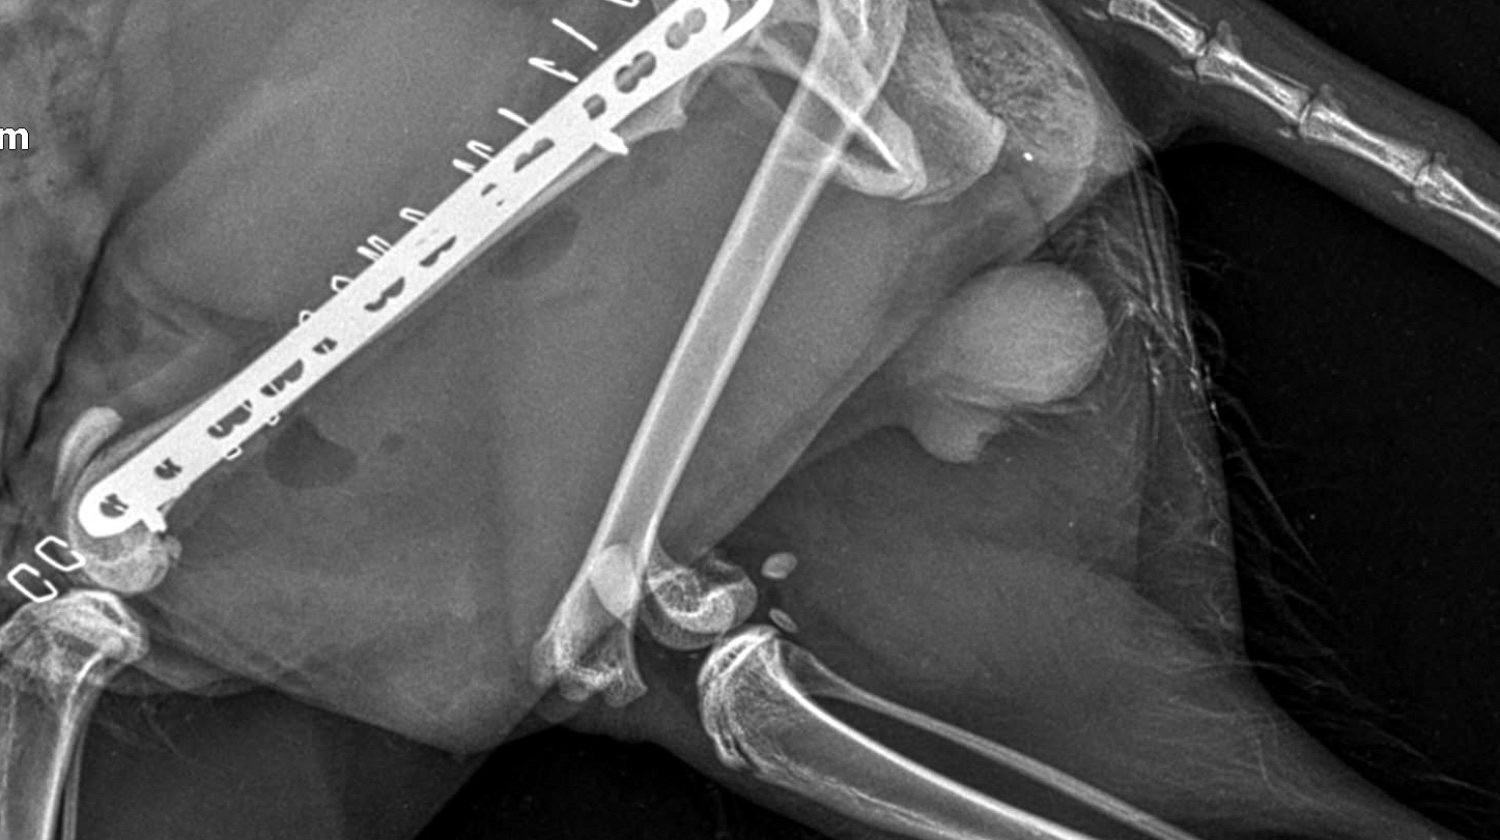

Lucky je maček, ki so ga pred nekaj dnevi našli pred blokom, v katerem živi moj brat. Luckyja je takoj odpeljal k veterinarju. Po posvetu je ugotovil, da ima poškodovani obe nogi in medenico :(. Natančneje, ima naslednje težave:

Medenica

obojestranska sakroiliakalna dismoreksija

Zlom desne iliakalke s premikom

Zadnje okončine

Diafizni zlom v srednji tretjini, poševni, s premikom, brez kostne eklatantnosti, na ravni stegnenice femurulolistangii

Zlom tipa SH I distalno od desne stegnenice

Slikovna diagnoza: zlom leve stegnenice, SH zlom desne stegnenice, obojestranski križno-iliakalni izpah, zlom desne iliakalne palete

Po opravljenih rentgenskih posnetkih, kjer so bile ugotovljene

zgoraj, so ga odpeljali k ortopedu in bo potreboval 3 operacije: po eno za vsako nogo + operacijo medenice.